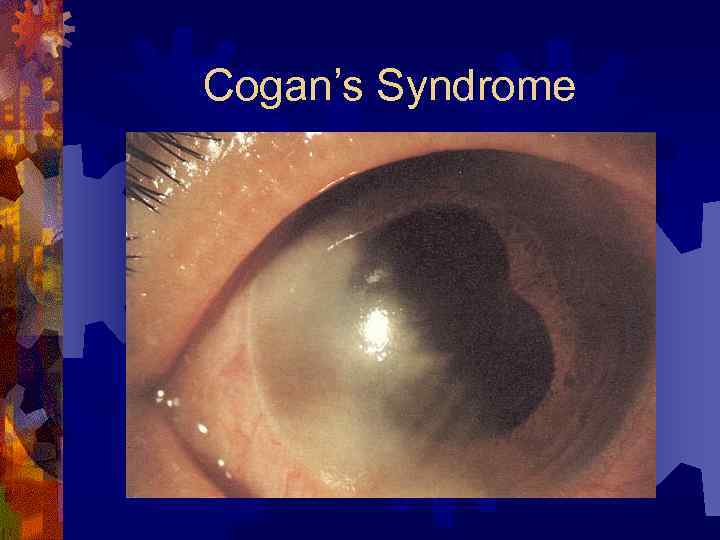

Синдром Когана (Cogan’s Syndrome) Аутоиммунное заболевание роговицы и внутреннего уха ® Начало – в возрасте 22 -29 лет ® Этиология неизвестна ® Прявления – интерстициальный кератит и Меньеро-подобные эпизоды ® У большинства (67%) больных – двусторонняя флюктуирующая потеря слуха ® Сопутствующие системные проявления: ® ® ® Аортит – 10% Терапия – ® ® Кортикостероиды – преднизолон 1 мг/кг Х 2 -4 нед Кохлеарная имплантация

Cogan’s Syndrome